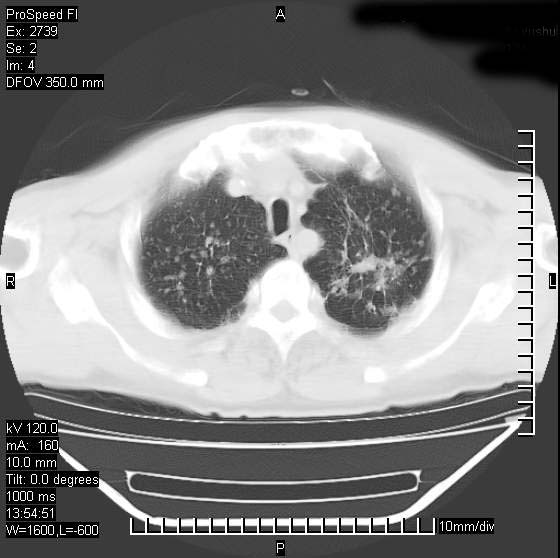

以下是引用andymaomao在2007-12-7 15:54:00的发言:[br]1.双上肺陈旧肺tb灶;[br]2.双中上肺矽肺;[br]3.双肺气肿;[br]4.图中箭头所指乃下腔静脉。

以下是引用山之魂海之韵在2007-12-7 18:59:00的发言:[br]支持矽肺,左肺上叶陈旧性结核,肺气肿。箭头所指乃下腔静脉。下腔静脉显影比主动脉显影迟,增强动脉后迟可以是不均匀的。

以下是引用chengjiaqiu1在2007-12-7 17:49:00的发言:[br]矽肺,左肺上叶陈旧性结核,肺气肿。中箭头所指乃下腔静脉。